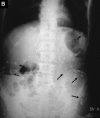

Subcutaneous cysticercosis